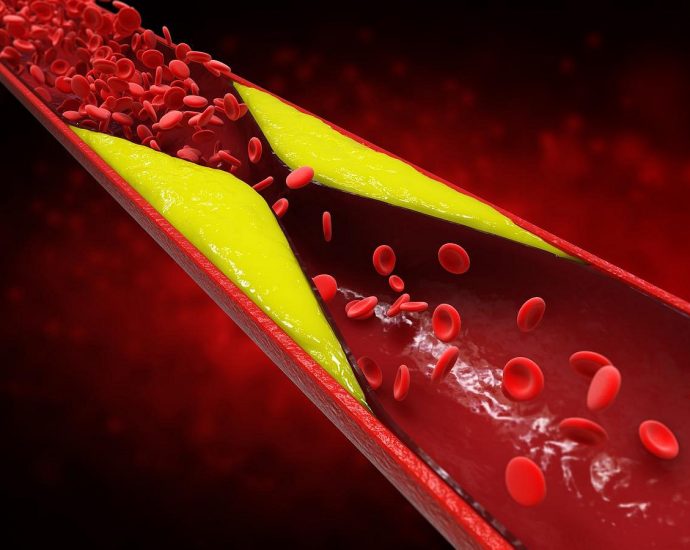

Most People Aren’t Aware Of Genetic Risk For Dangerously High Cholesterol

FRIDAY, Nov. 21, 2025 (HealthDay News) — Most folks with genetics that put them at risk for high cholesterol and early heart disease aren’t aware of their danger, a new study says. Nearly 90% of people carrying genetics that cause dangerously high cholesterol — an inherited condition called familial hypercholesterolemiaContinue Reading